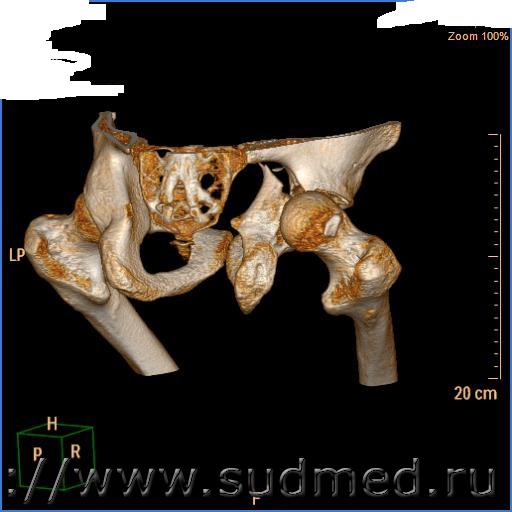

Для проведения экспертизы мне сказали надо веские основания для ее проведения, которые надо передать в отдел полиции. Я пошел в гор.больницу, где был на излечении и взял снимки КТ с описанием этих снимков - на основании этого описания мне в акте СМО поставили вред СРЕДНЕЙ тяжести (во время поступления: "Визуализируется оскольчатый перелом правой вертлужной впадины с задним вывихом бедренной кости и перелом правой седалищной кости без смещения отломков", после вправления вывиха "Оскольчатый внутрисуставной перелом правой подвздошной кости без смещения.Вывих правого бедра вправлен, соотношение в суставе правильное")

Меня в бюро СМЭ сразу предупредили, что если не будет в описании смещения то степень тяжести останется СРЕДНЕЙ. Я обратился к своему лечащему врачу для на основании снимков он поставил развернутый и однозначный диагноз - он поставил " Внутрисуставной оскольчатый перелом правой подвздошной кости со смещением отломков задней полости правой вертлужной впадины кзади". Но как оказалось диагноз лечащего не так принципиален, а смотрят впервую очередь на описание рентгенолога. Я снова пощел в горбольницу и попросил сделать описание снимков с учетом того есть смещение отломков или нет. Мне выдали теперь те же описания, за той же датой и номером но уже (во время поступления: "Визуализируется оскольчатый внутри суставной перелом ТЕЛА правой вертлужной кости со смещением и задним верхним вывихом правого бедра и перелом правой седалищной кости без смещения", после вправления вывиха "Оскольчатый внутрисуставной перелом правой подвздошной кости, смещение устранено. Перелом правой седалищной кости без смещения. Вывих правого бедра вправлен, соотношение в суставе правильное"). Хотя на снимках отчетлива видны отломки которые не устранены

СНИМКИ Прилагаю (правда качество не очень)

Судебная медицина - Прикрепленное изображение Судебная медицина - Прикрепленное изображение Судебная медицина - Прикрепленное изображение Судебная медицина - Прикрепленное изображение Судебная медицина - Прикрепленное изображение

Не могу разобраться.Качество неважное.

КТ нельзя оценивать по 3-Д реконструкции. Нужно смотреть все срезы, записанные на диск, знать какой шаг, укладка ...

Качество представленных Вами здесь 3D-реформаций не позволяет сделать никаких выводов: изображение раплывчатое, т.к. переснято камерой с небольшим числом пикселей или с неверно выставленными условиями съемки (плохая фокусировка). Если есть возможность, то получите у рентгенолога все сканы КТ на флешке или CD-диске (из памяти компьютера томографа или с архивной записи на CD). Либо качественно переснимите все сканы с пленок. Что бы на экране компьютера они не выглядели как просматриваемые через полуматовое стекло.

Да мне вообще показалось что вертлужная впадина не повреждена. Где там её осколки ...???

И где там вывих?

Уж вывих даже и на мутном снимке не прозеваешь. Головка бедренной кости на всех снимках на месте.

Где вывих, коллеги?